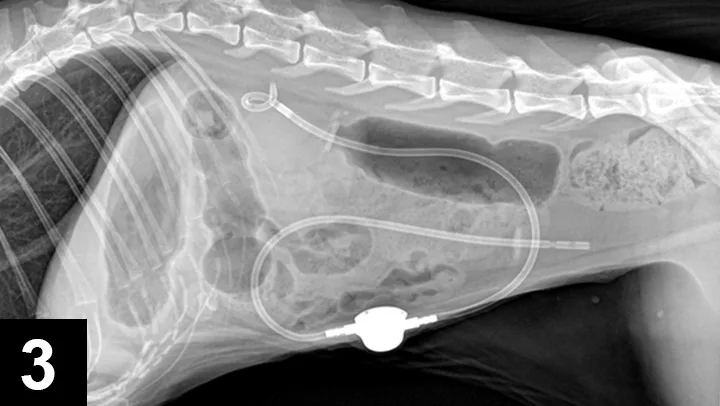

The use of SUB devices has become more common. They are typically used in feline patients with ureteral obstructions (Figure 3) and are preferred when compared with ureteral stenting in cats. An indwelling SUB device can be created using a cystostomy catheter and a combination locking-loop nephrostomy catheter. This device was modified after reports in human medicine described a nephrostomy tube that could remain indwelling for longer periods.

Figure 3. Lateral radiograph of a cat with a SUB device. The locking loop pigtail catheter connecting the subcutaneous shunting port is connected to a straight cystostomy catheter, allowing for a ureteral bypass.

The device has a subcutaneous shunting port that can be sampled and flushed as needed. In humans, a similar device has been shown to reduce complications associated with externalized nephrostomy tubes and improve quality of life.2 SUB devices have been placed in more than 150 feline and canine patients in the author’s practice with favorable results and are now the preferred treatment for feline ureteral obstructions. In dogs, the device is reserved for when stent placement fails. The perioperative complication rate associated with SUB devices has declined with the development of a commercially available device (<10%).